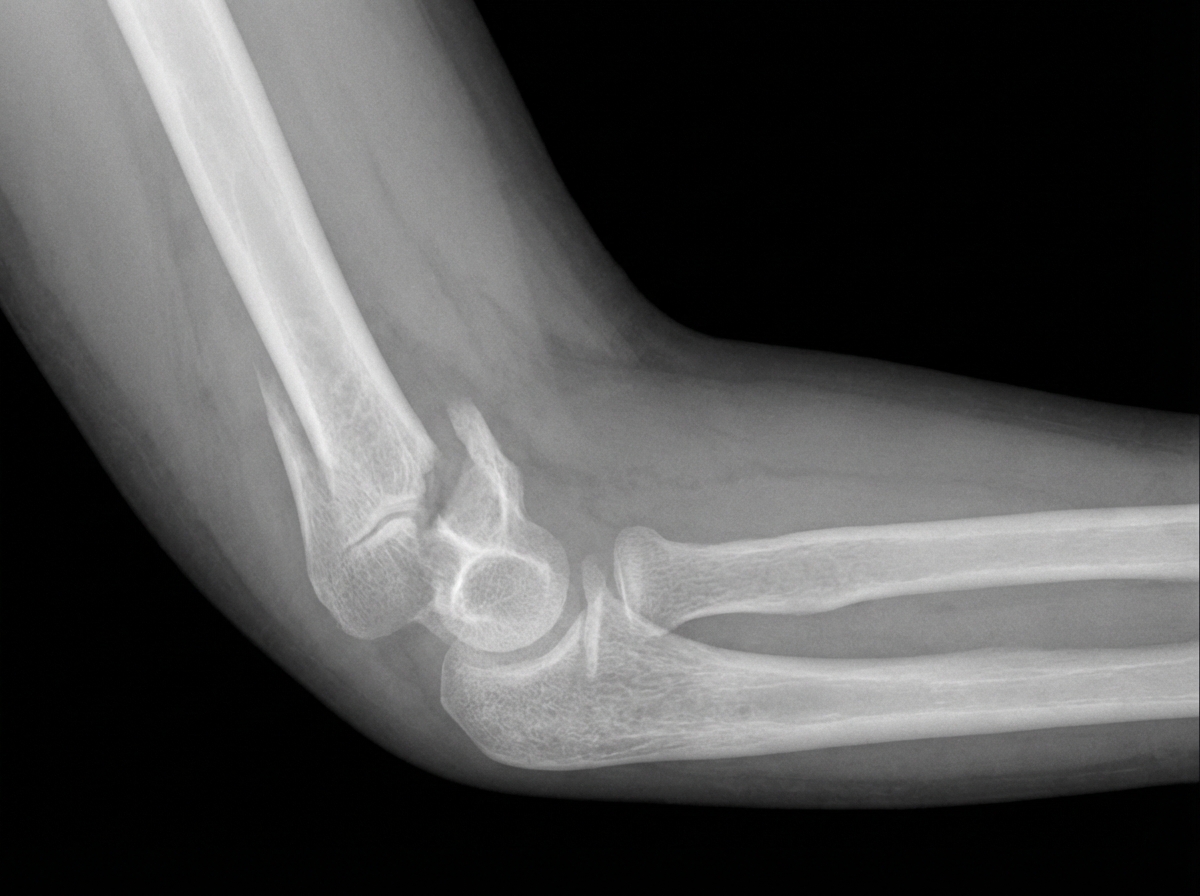

An 8-year-old boy is brought to the emergency department after falling from a trampoline and landing on his left arm. On presentation, he is found to be holding his left arm against his chest and says that his arm is extremely painful just above the elbow. Radiographs are obtained showing the finding in figure A. The boy's arm is reduced and placed into a splint pending surgical fixation. If this patient's fracture is associated with a nerve injury, which of the following actions would he most likely be unable to perform in the emergency department?